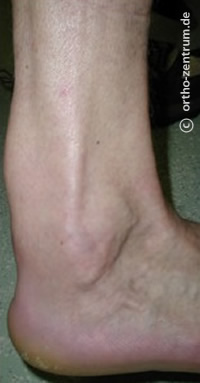

Schmerzhafte Achillessehne (Achillodynie), Haglund-Ferse und Fersensporn

Der Ansatzbereich der Achillessehne an der Ferse ist häufig schmerzhaft, insbesondere bei sportlich Aktiven, da es sich hierbei um die am stärksten belastete Sehne des menschlichen Körpers handelt.

An der Achillessehne stehen ein Vielzahl von nicht-operativen Maßnahmen zur Verfügung, die ausgeschöpft werden können. Einen schmerzhaften Knochenvorsprung (Haglund-Exostose) kann man operativ abtragen. Ein Fersensporn wird am Besten zunächst durch nichtoperative Maßnahmen therapiert.